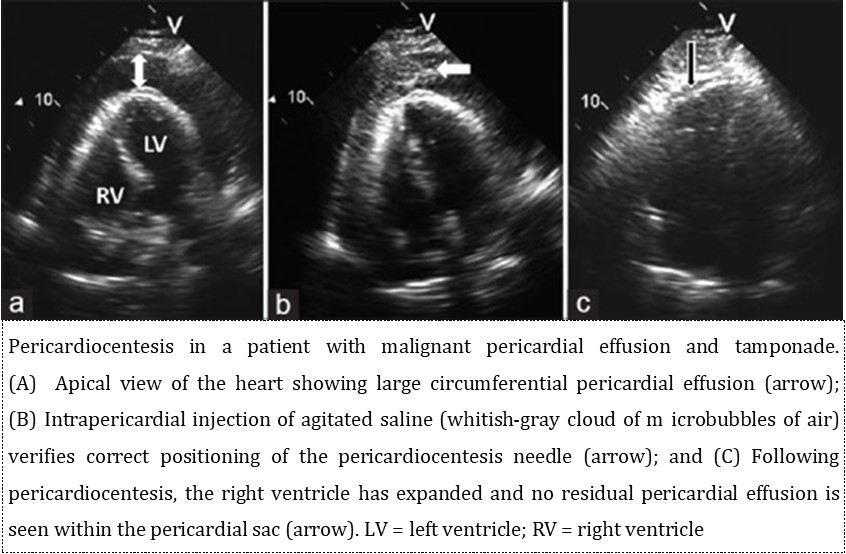

Knowledge of accurate surface anatomy is essential for safe clinical practice. Different views and opinions for clinically important surface markings exist between clinicians. Pericardiocentesis is performed as an emergency procedure in conditions aggravating cardiac tamponade. The approach of pericardiocentesis should be held by the hands of an experienced operator because of the surrounding relations. Nowadays, the introduction of imaging-guided procedures, especially echo-guided procedures, has significantly improved the safety and feasibility of pericardiocentesis and has provided the possibility of choosing the best anatomical approach among the apical, subcostal and parasternal approaches. This case report also emphasizes the importance of instillation of agitated saline as a supplementary technique while performing echo-guided pericardiocentesis in order to reduce the likelihood of cardiac chamber perforations.

Pericardiocentesis is the most useful therapeutic procedure for the early management or diagnosis of large, symptomatic pericardial effusion and cardiac tamponade 1. The first description of cardiac decompression was in 1653, when Riolanus suggested sternal trephination to relieve pericardial pressure. In 1911, Marfan first described the subxiphoid approach, which had been used for the blind pericardiocentesis procedure for decades, despite the significant morbidity and mortality rates (50% and 6%, respectively) 2. In the subsequent years, the techniques recommended for a safe and successful pericardiocentesis have changed considerably, particularly with the introduction of fluoroscopic, electrocardiographic and, finally, echocardiographic guidance 3, and with the description of approaches other than the substernal one (apical and parasternal). Pericardiocentesis is performed as an emergency procedure in conditions aggravating cardiac tamponade, or as a part of the diagnostic workup of cryptogenic pericardial effusion 1.Accurate surface anatomy is essential for safe clinical practice. Different views and opinions for clinically important surfacemarkings exist between clinicians. Percutaneous pericardiocentesis was first performed in 1840 by Frank Schuh 2. The subxiphoid approach was adopted in 1911 but because the procedure was performed ‘blind’, it was associated with high rates of complication3. Advanced fluoroscopicand ultrasonic techniques, helped to reduce the complication rates associated with pericardiocentesis between 0.5 and 3.7% 4, 5, 6. Echocardiography has been given class l recommendation by a 2003 task force of the American Heart Association (AHA), and the American Society of Echocardiography (ASE) 7. Echocardiographic diagnosis of pericardial effusion confirms the clinical diagnosis of acute pericarditis. This should be performed prior to performing a pericardiocentesis to document the location and the size of the effusion. Echocardiography can detect an effusion as small as 30 cc 8.

Pericardiocentesis: Anatomic structures and approaches are as follows, the pericardium is composed of visceral and parietal components. The pericardial space is enclosed between these two serosal layers and normally contains up to 50 mL of plasma ultra-filtrate, the pericardial fluid 8. The approach of pericardiocentesis should be held by the hands of an experienced operator because of the surrounding relations (Figure 2). Anteriorly, the fibrous pericardium is separated from the thoracic wall by the lungs and the pleural coverings. The direct contact of the pericardium with the thoracic wall is observed in a small area behind the lower left half of the body of the sternum and the sternal ends of left fourth and fifth costal cartilages.

Infra-sternal angle (Subcostal Angle) is at the two subcostal margins enclose or meets ups in the infra-sternal angle. The xiphoid process lies in the shallow depression of infra-sternal angle. The xiphisternal joint is represented by a transverse ridge at the apex of the infrasternal angle.Costal margin is formed by the union of the upturned ends of the cartilages of tenth, ninth, eighth and seventh ribs. The costal margin is usually visible through the skin. Lateral margins of the sternum can be felt indistinctly at the sternal ends of the second,third and fourth intercostals spaces 14.Following pericardiocentesis, repeated echocardiography and continued hemodynamic monitoring are useful to assess reaccumulation. The duration of monitoring is amatter of judgement but typically 24 hours is sufficient 8.Echocardiography-guided pericardiocentesis is a safe and simple technique, introduced at the Mayo Clinic in 1979 and widely used nowadays 18.

The echocardiography-guided approach allows defining the position of the effusion, the ideal entry site and needle trajectory for pericardiocentesis. There are two different approaches to echo guidance: the first is the echo-assisted method, in which the operator memorises the optimal needle trajectory and advances the needle towards the pericardial space without a continuous ultrasound visualisation. The second approach is the echo-guided method with a continuous echocardiographic monitoring. It has also been proposed to use a needle carrier mounted on the ultrasound transducer to advance the needle to the pericardial space 18, 19.